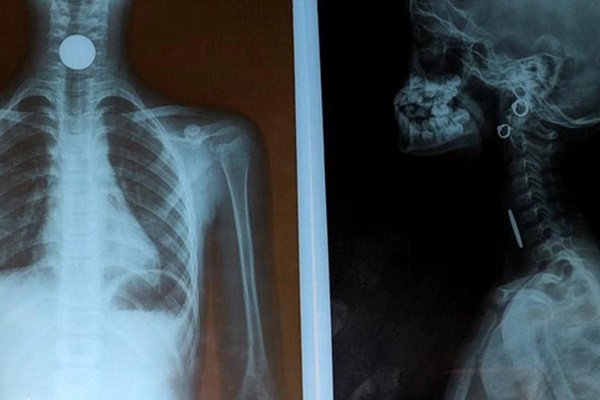

Khi bệnh nhân đến khám tại Bệnh viện Đa khoa Đồng Nai, kết quả chụp X-quang cho thấy có dị vật ở phổi bệnh nhân, làm cho thuỳ trên phổi phải bị đông đặc hoàn toàn.

Các bác sĩ quyết định nội soi khẩn cấp, gắp dị vật phát hiện hạt hồng xiêm dài khoảng 3cm, gây tắc hoàn toàn 1/3 phổi. Do dị vật dẹt có ngạnh, trơn trượt, găm vào thành phế quản nên rất khó gắp ra.

Hơn 2 giờ đồng hồ dùng các kỹ thuật và nhiều dụng cụ khác nhau, các bác sĩ đã lấy được hạt hồng xiêm thành công ra khỏi phổi bệnh nhân.